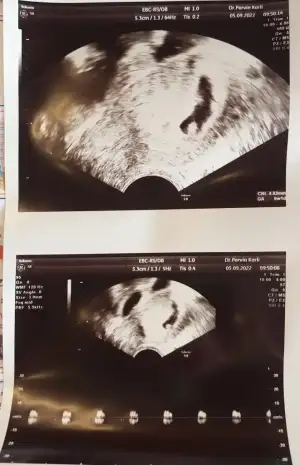

Kızlar güzel haberlerim var. Yeni bir doktora gittik ve alttan muayene etti kalp atışını duydukkk💖 beklemiyorduk daha erken. Şimdiye kadar neden değiştirmedik diye kendimi çok kızdım. Karşımıza çok iyi bir doktor çıktı. Çok şükür içimiz rahatladı bebeği de gördük kalp atışını da duyduk.